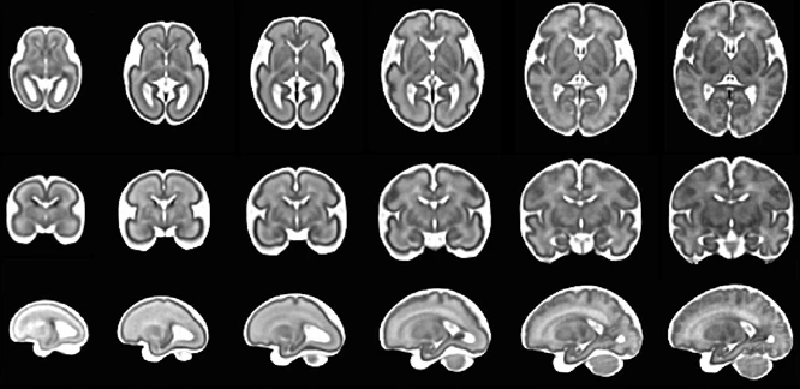

MRI ΚΝΣ εμβρύου

Μαγνητική τομογραφία ΚΝΣ εμβρύου